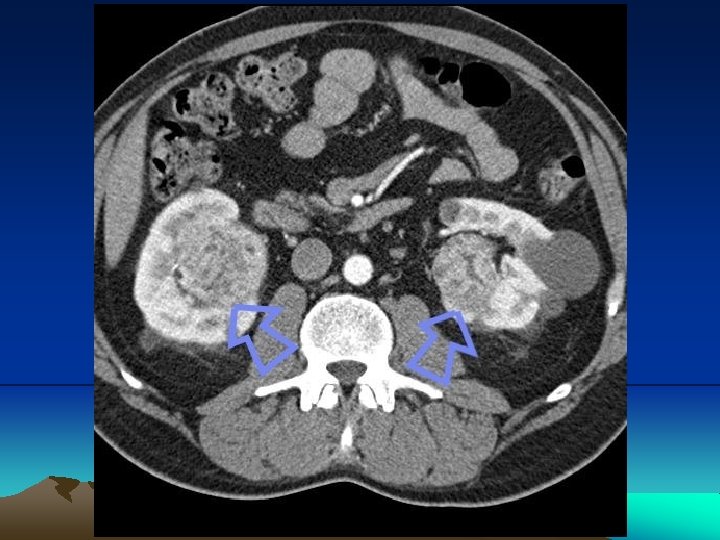

Renal lymphoma has an insidious clinical presentation that occurs late in the course of the disease. It can present in many ways, however the most common are primary tumors presenting single or multiple nodules, or that involve the kidney, either in a hematogenic dissemination form or through a contiguous retroperineal disease

Primary renal Iymphoma